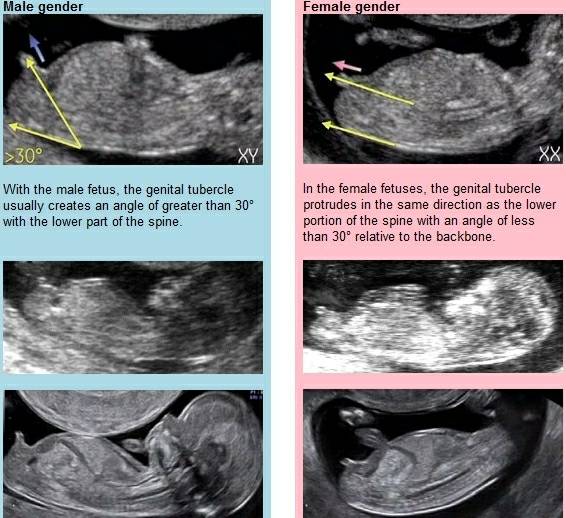

Można zacząć podejrzewać co do płci dziecka, ale na tym etapie to jeszcze za wcześnie na diagnozy ze 100% pewnością, bo narządy nie są jeszcze wykształcone, strzela się na podstawie wyrostka płciowego płodu. Tylko sama zobacz na zdj jak to wygląda na zdj. U chłopca jest pod kątem większym niż 30stopni, u dziewczynki pod katem mniejszym niż 30stopni. Tu też trzeba pamiętać że USG to obraz na podstawie odbitych promieni, czyli też nie do końca dokladny, no i może być źle zmierzone, na oko. Można sugerować, ale to nic pewnego jeszcze na tym etapie